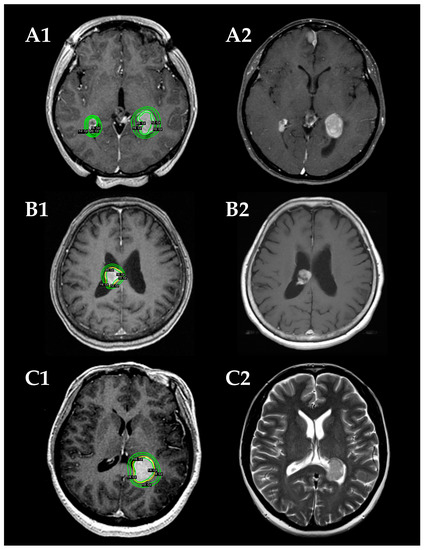

The Leksell Gamma Knife (Elekta Instruments, Stockholm, Sweden) was used for all SRS procedures. The detailed treatment process has been previously reported [15,16]. After head fixation using a Leksell frame (Elekta Instruments), stereotactic imaging (computed tomography [CT] before July 1996, magnetic resonance imaging [MRI] between August 1996 and January 2018, followed by cone-beam CT) was performed to obtain precise tumor data. Dedicated neurosurgeons and radiation oncologists performed radiosurgical planning using commercially available software (KULA planning system until 1998 and Leksell Gamma Plan thereafter [Elekta Instruments]). In principle, 16 Gy before 2010 and 14 Gy thereafter were administered to the tumor margin using a 50 ± 5% isodose line. Representative cases are shown in Figure 1.

Figure 1.

Radiosurgical plans (A1–C1) and follow-up magnetic resonance images (MRIs) (A2–C2) in three demonstrative patients. (A) A 31-year-old woman with NF2-related bilateral intraventricular meningiomas (IVMs) in the trigones of the lateral ventricles (cases 7 and 8). The tumors are stable in size on a follow-up MRI at 21 months after the stereotactic radiosurgery (SRS). (B) An 80-year-old woman with a sporadic IVM in the body of the right lateral ventricle (case 9). Tumor shrinkage is confirmed on a follow-up MRI at 109 months after the SRS. (C) A 50-year-old woman with a sporadic IVM in left trigone (case 11). Tumor shrinkage is confirmed on a follow-up MRI at 35 months after the SRS.